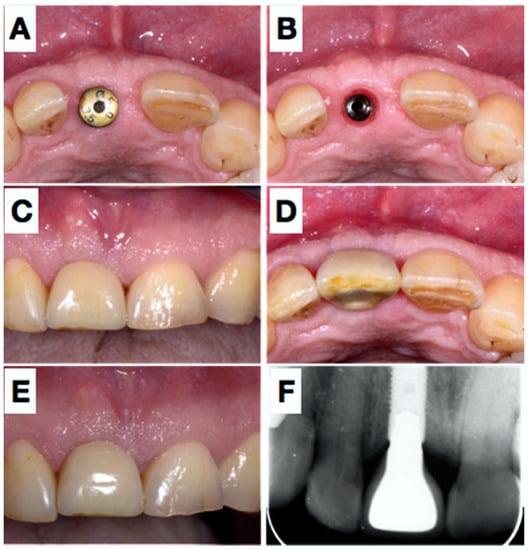

Sutures were removed after 7 days and wound healing was again uneventful. In addition, regular wound controls were performed and showed completely non-irritated mucosal conditions. Six months postoperatively, the abutment connection was performed (Figure 4). The mucosal region 11 over the abutment was de-epithelised and a U-shaped incision was made. A minimally invasive roll flap was performed and stabilized with the healing abutment. No sutures were used.

Figure 4.

After 6 months submerged healing of the implant (A,B), the mucosa was de-epithelialized (C) and a roll-flap was made to uncover the implant (D); a healing cap was placed, which held the buccally advance flap in situ. Situation after 3 weeks (E,F).

For aesthetic reasons, the neighboring teeth 21 and 12 were adapted with composite. The final impression was made with a polyether (Permadyne, Espe) in an open tray and at the same time the bite taken with a polyvinylsiloxane. Due to the excellent peri-implant conditions, conditioning of the mucosa was not required and 5 weeks after impression, a screw-retained crown could be inserted (Figure 5). The insertion torque was 25 Ncm. After 4 weeks, the prosthetic screw was retightened again with 25 Ncm at a final check appointment. The screw access channel was closed with a Teflon membrane and composite resin.

Figure 5.

5 weeks later (A), the healing abutment was removed (B) and an impression was taken. Panels (C,D) show the situation after placement of the definitive crown placement (screw-retained) and the result two years later, clinically and radiographically (E,F).